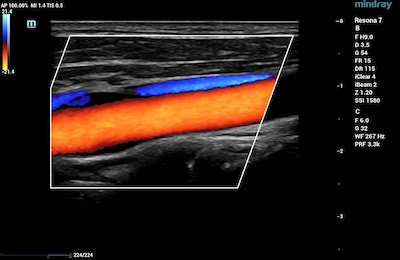

- Blood Vessels – Vascular ultrasound is used to evaluate the circulatory system. CDI is used to diagnose and stage acuity of clots in the veins, as well as venous reflux. It is also useful to assess narrowing and blockages within a patient’s arteries.

Color Doppler of Common Carotid Artery